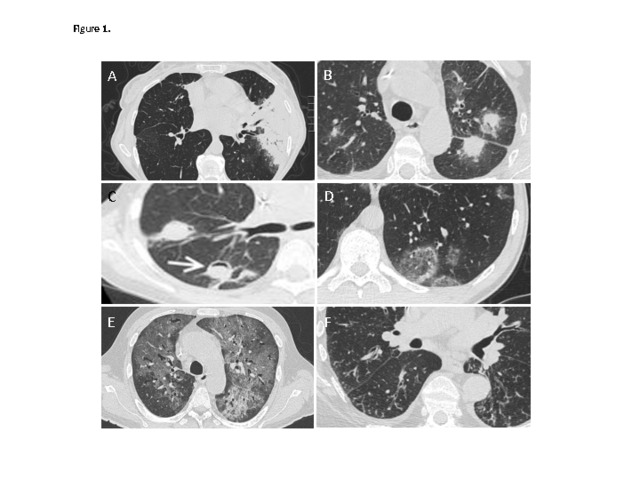

Respiratory complications, in particular infections, are common in the setting of hematological malignancy and after hematopoetic stem cell transplant. The symptoms can be nonspecific; therefore, it can be difficult to identify and treat the cause. However, an understanding of the specific immune defect, clinical parameters such as speed of onset, and radiological findings, allows the logical diagnostic and treatment plan to be made. Radiological findings can include consolidation, nodules, and diffuse changes such as ground glass and tree-in-bud changes. Common infections that induce these symptoms include bacterial pneumonia, invasive fungal disease, Pneumocystis jirovecii and respiratory viruses. These infections must be differentiated from inflammatory complications that often require immune suppressive treatment. The diagnosis can be refined with the aid of investigations such as bronchoscopy, computed tomography (CT) guided lung biopsy, culture, and serological tests. This article gives a schema to approach patients with respiratory symptoms in this patient group; however, in the common scenario of a rapidly deteriorating patient, treatment often has to begin empirically, with the aim to de-escalate treatment subsequently after targeted investigations.